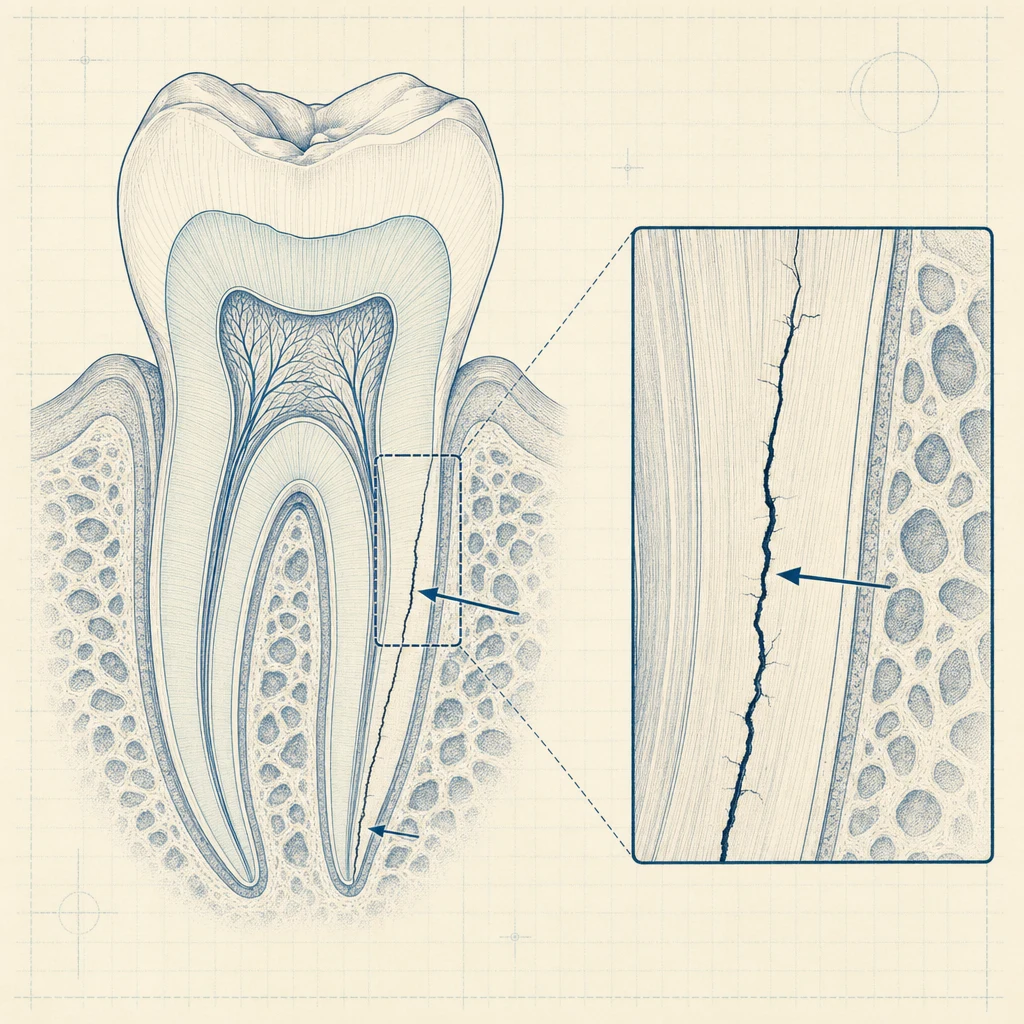

2. 치근 균열 (Vertical Root Fracture)

신경 제거 후 치아는 영양 공급이 끊겨 점차 단단함이 줄어듭니다. 보철을 미루면 강한 저작력에 의해 치근에 미세 균열이 생길 수 있습니다. 균열은 일반 X-ray에 잘 보이지 않아 정밀 검사가 필요합니다.